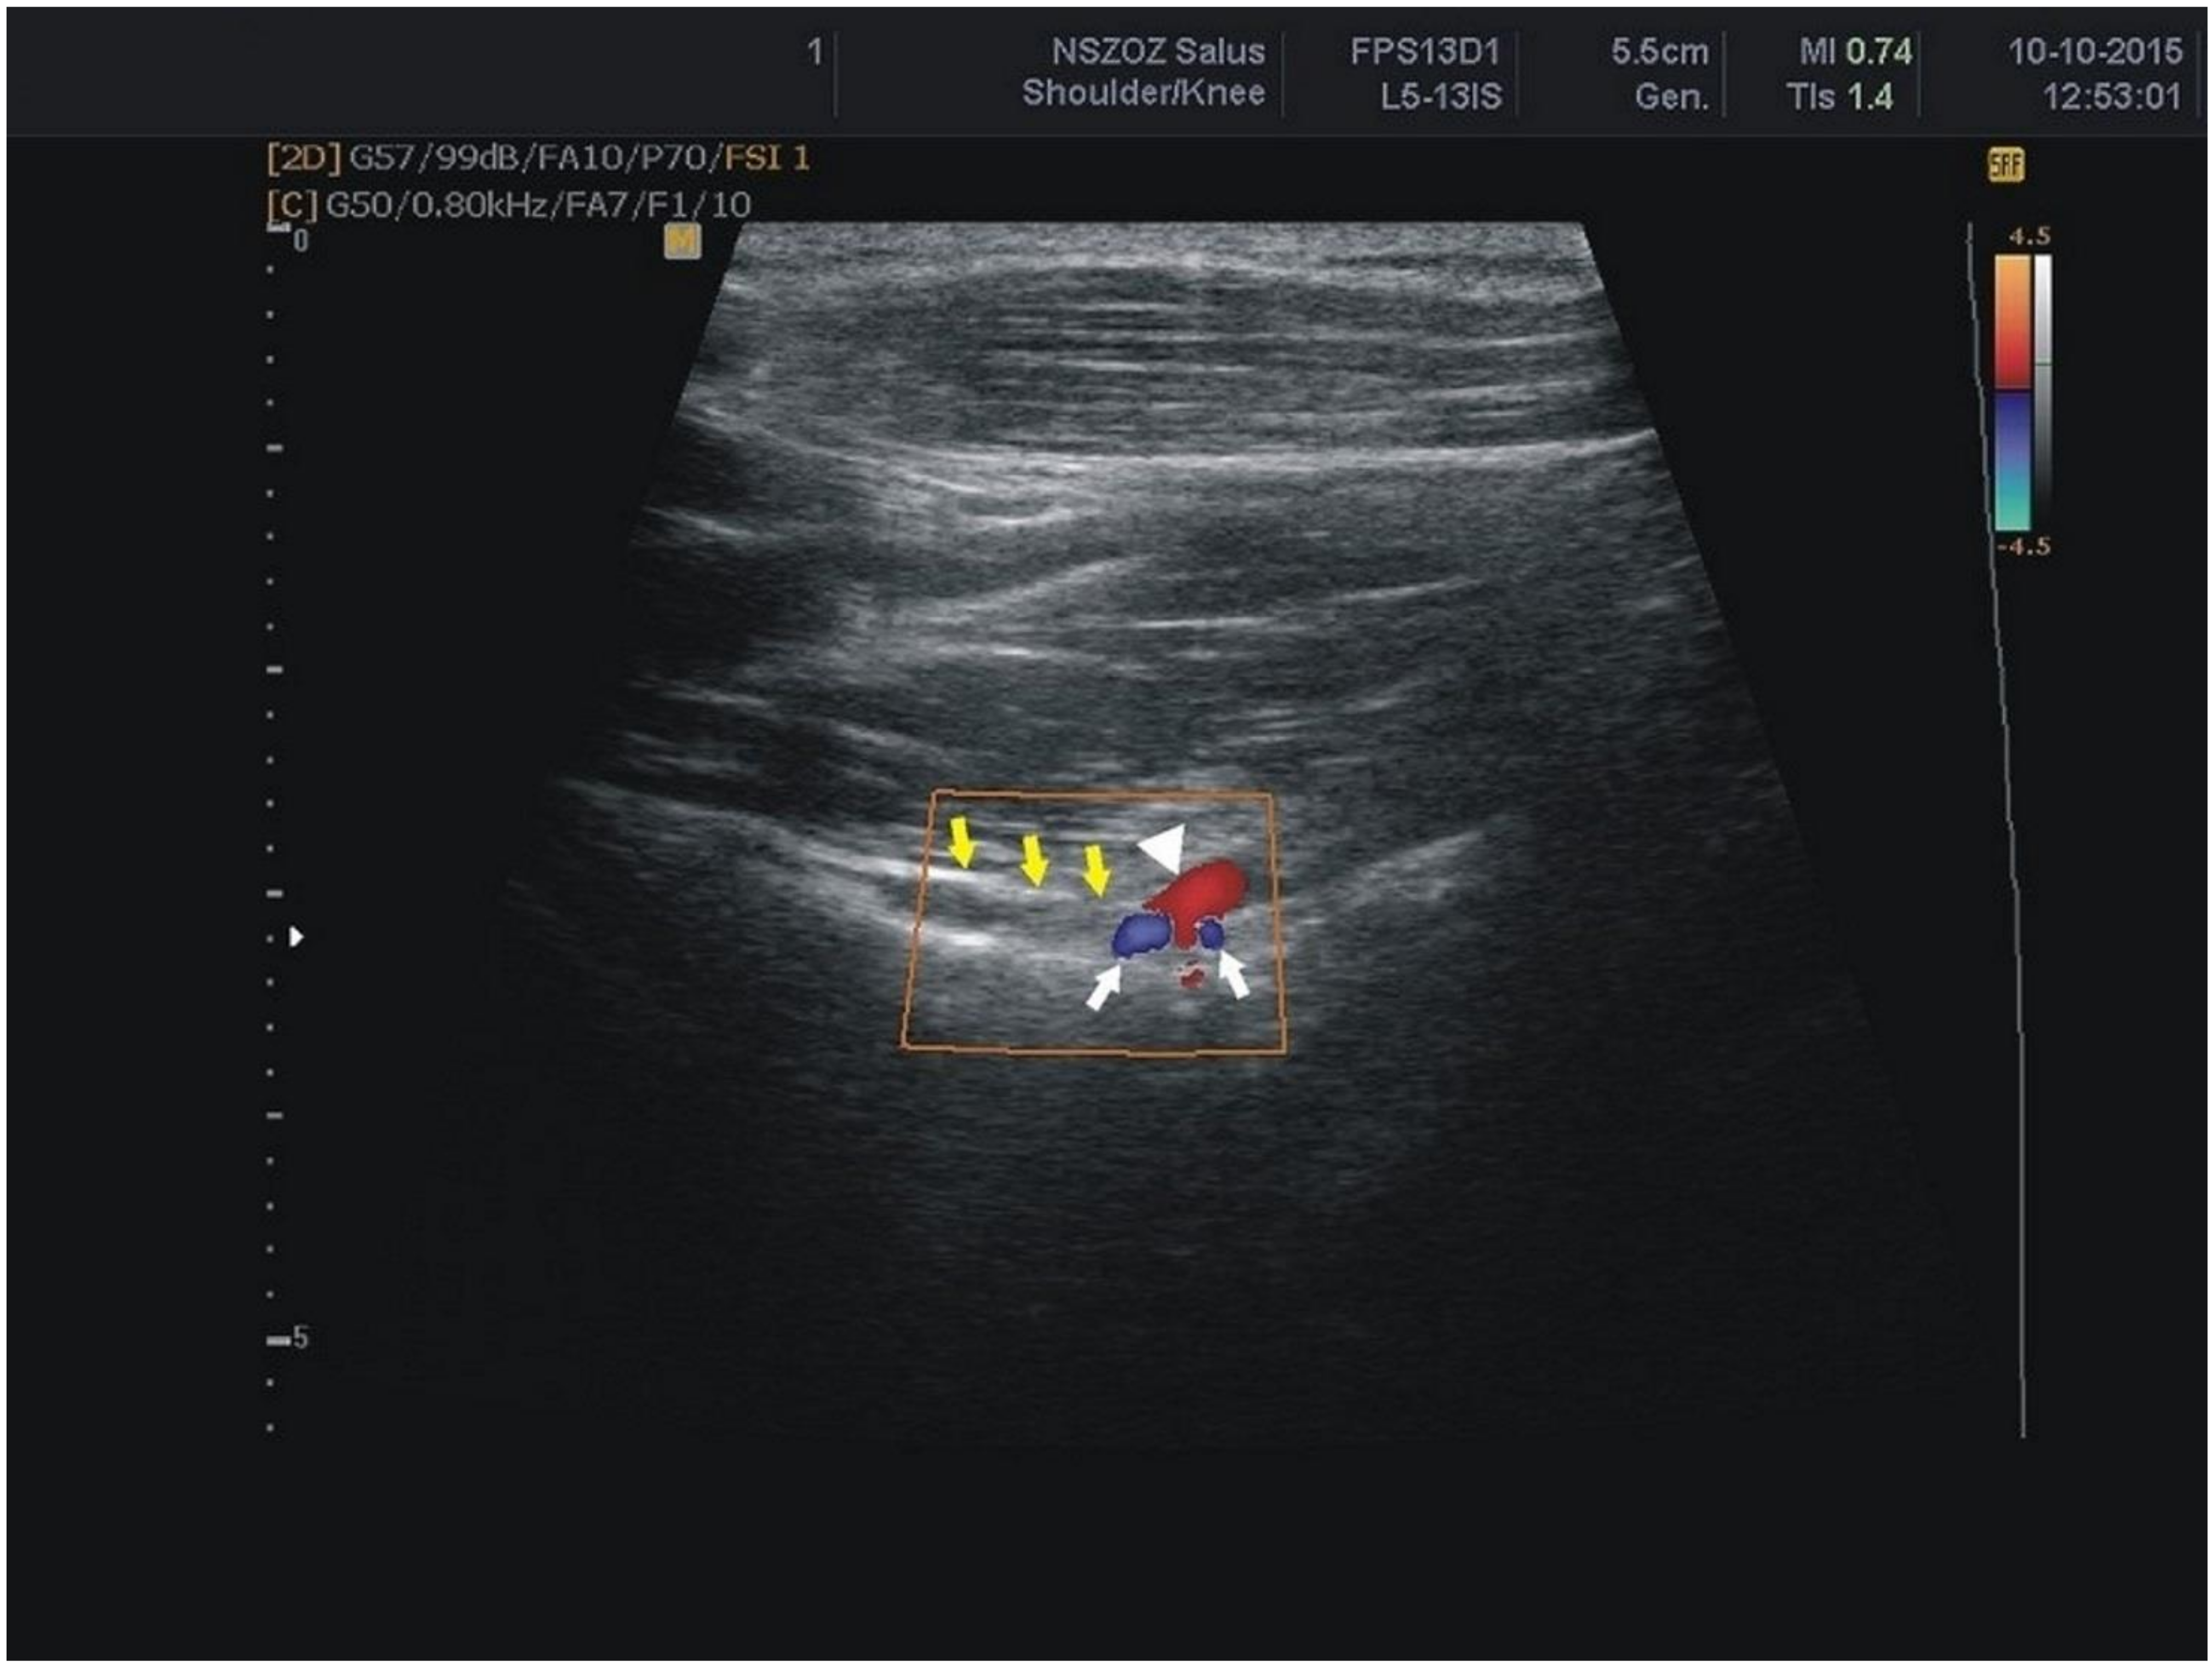

Figure 6.

Sonogram of the suprascapular notch region (color Doppler) white arrows: suprascapular veins; arrowhead: suprascapular artery; yellow arrows: superior transverse scapular ligament.

The suprascapular artery was recognised in all of the visualised notches (Figure 6). The suprascapular vein was visible more often than the suprascapular nerve (74.9% versus 48.1%) (Figure 6) (Table 2). There was a significant correlation between the BMI and thickness of the soft tissue over the suprascapular artery and vein (Table 3).

Suprascapular nerve block performed close to the nerve was more effective than blind injection in the suprascapular fossa. The specificity of the small area of the suprascapular region means that ultrasound plays a key role in any examination, especially when recognising the suprascapular nerve [17,19]. Visualisation of the suprascapular artery and vein is also needed to prevent unexpected bleeding during blockade procedures. A color Doppler study by Yücesoy et al. [30] identified the artery–vein suprascapular complex passing through the SSN in 86% of shoulders. In the present study, the distinction between vein and artery was made on the basis of flow spectrum analysis. Our four-step ultrasonographic protocol allowed the suprascapular artery to be found in all of the visualised suprascapular notches. In contrast, the suprascapular vein was visible only in 176 scapular notches (74.9%). It may be due to slower blood flow than in the artery, and the increased thickness of the soft tissue over the suprascapular vein, which correlated with the BMI.